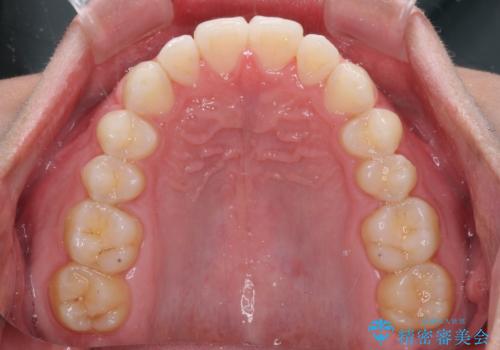

前歯のデコボコとクロスバイト インビザライン矯正治療

- 前歯のデコボコとクロスバイトを治したいとのことで来院された患者様です。

上下顎ともに歯列全体の側方拡大を行い、下顎前歯はIPR(歯と歯の間を削る)によってデコボコとクロスバイトが解消するように設計し、インビザラインにより治療を行うこととしました。